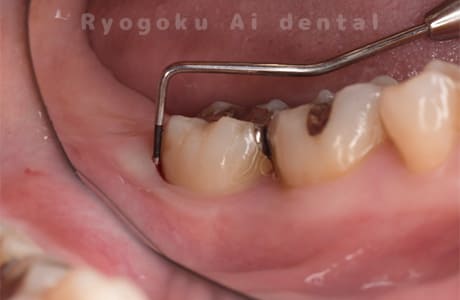

STEP 1

- 歯周ポケットの確認

プローブで歯周ポケットの状態を確認します。

- 歯の動きが大きい場合は下記の写真のようにワイヤーで固定する場合があります。